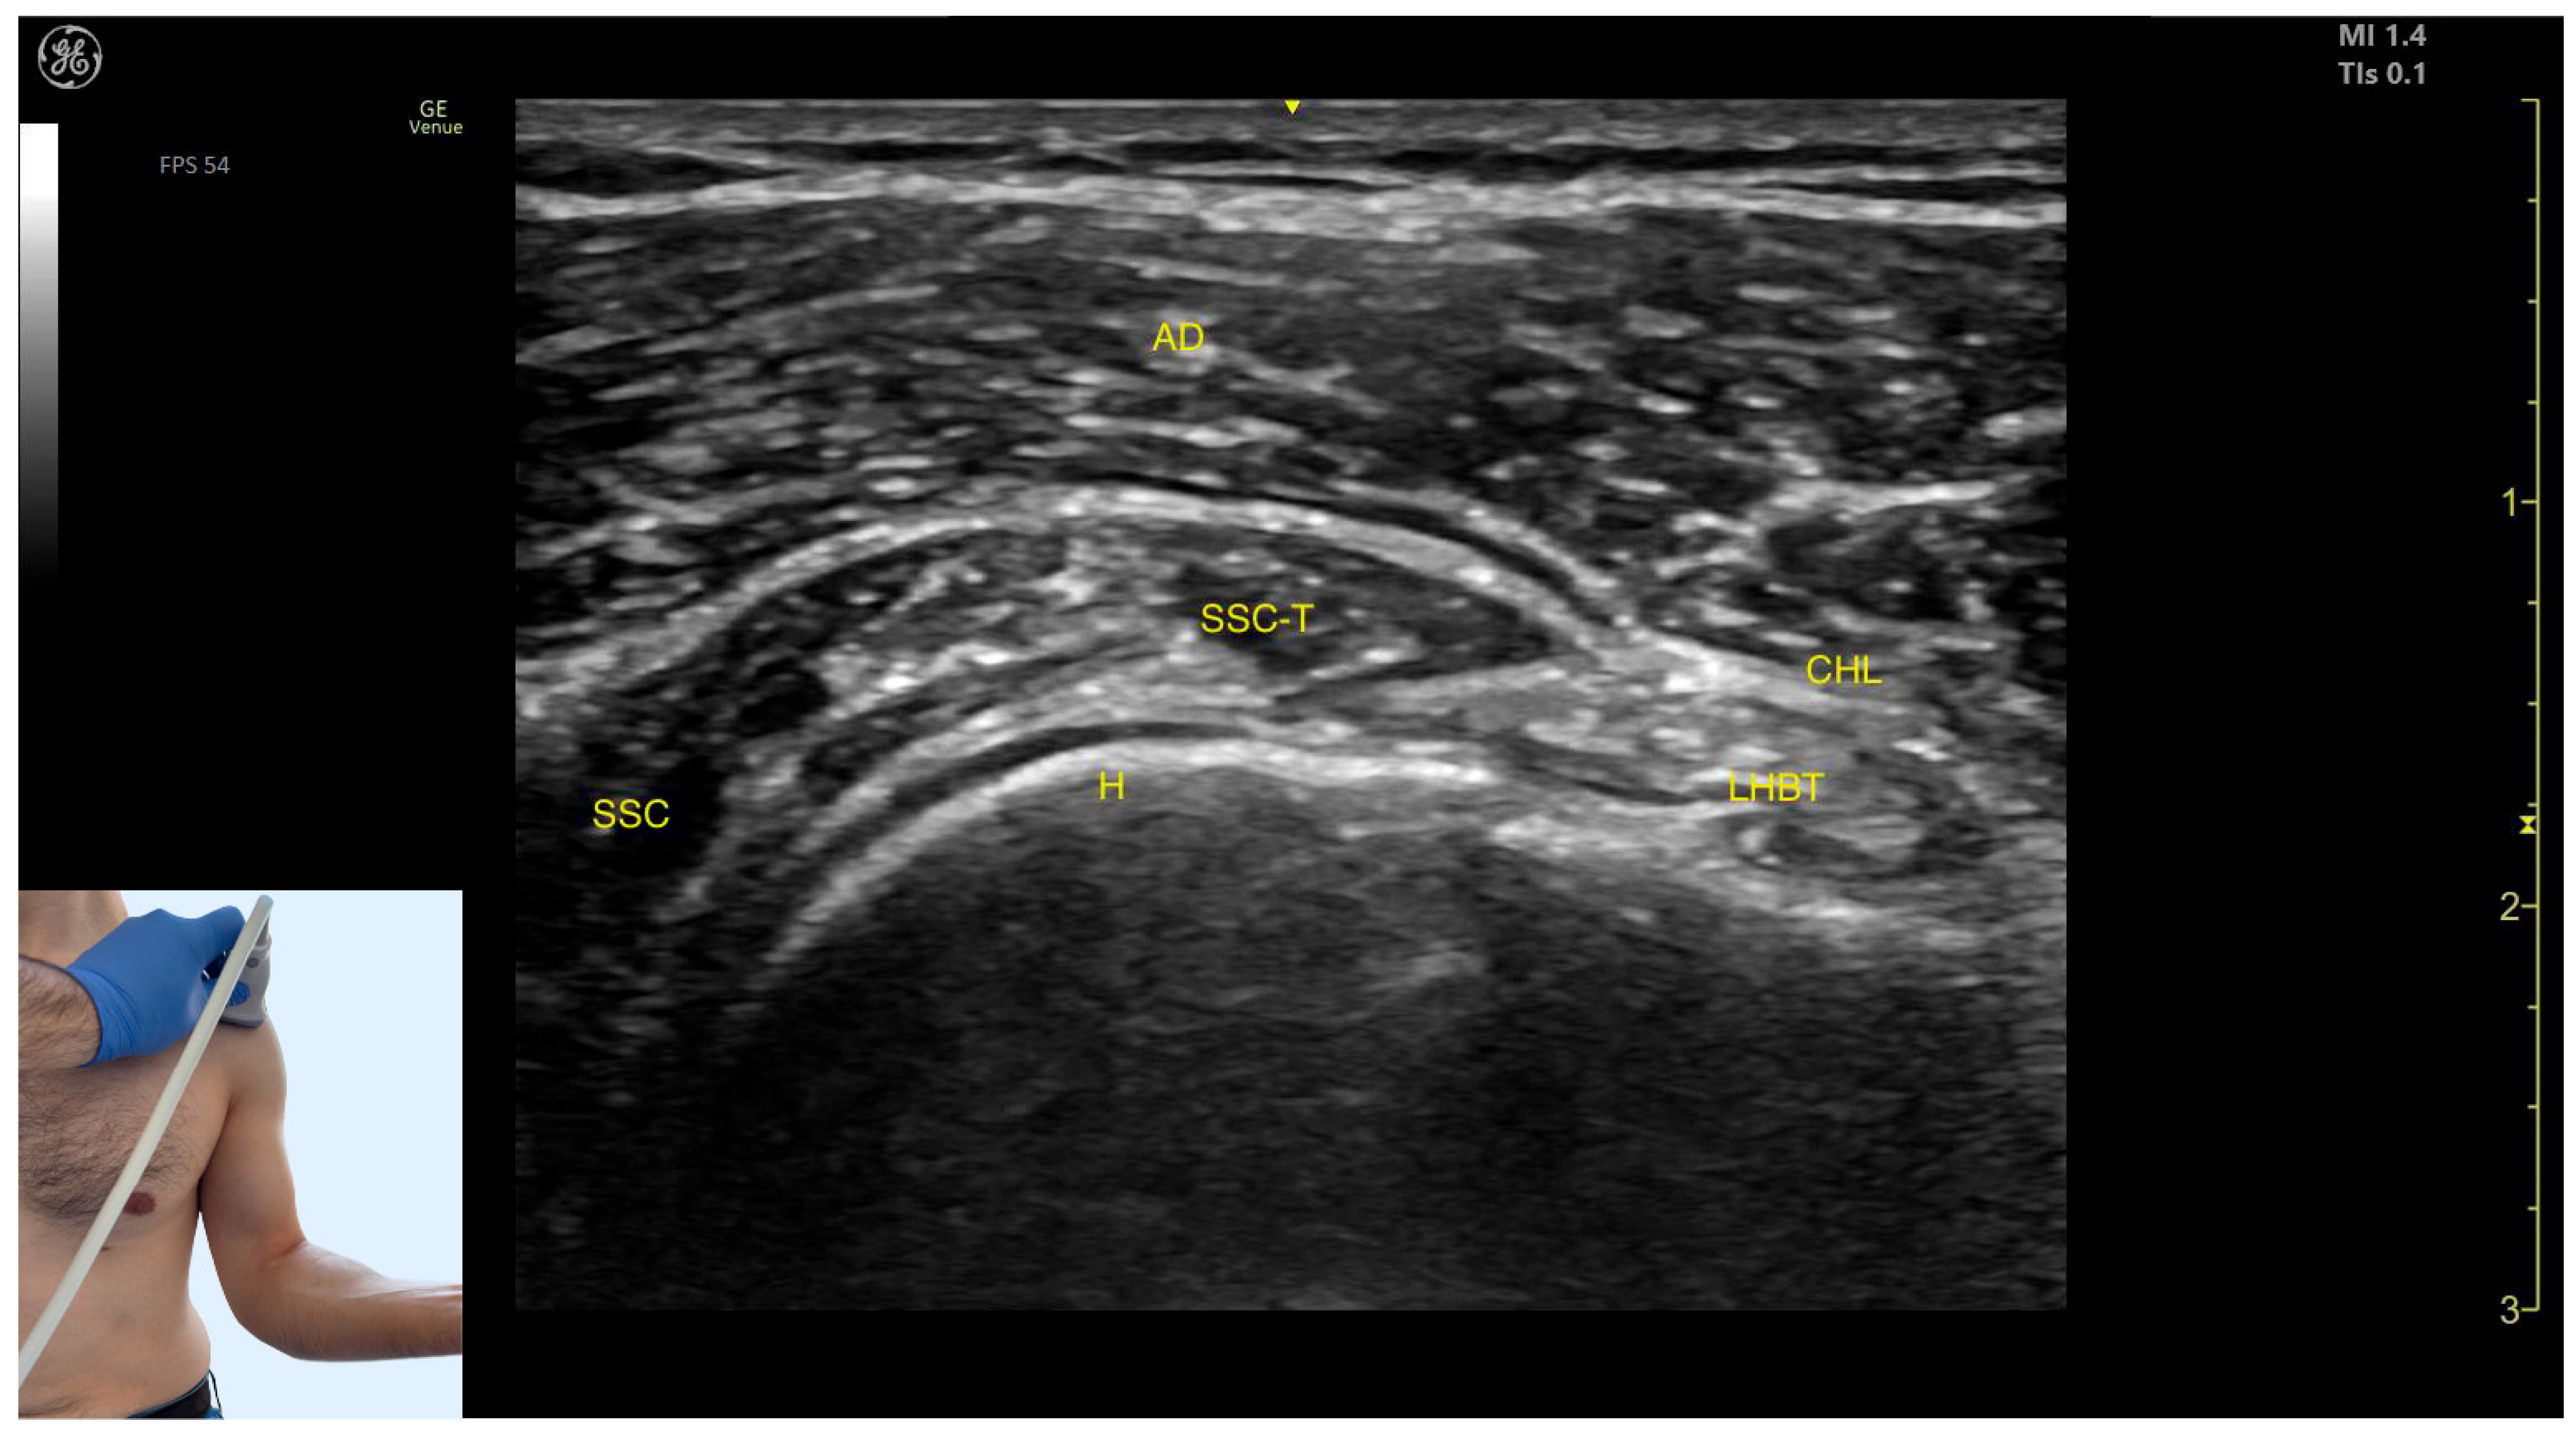

- Superficial to the humeral cortex, the long head tendon of the biceps brachii (LHBT) can be seen, encased by the coracohumeral ligament (CHL).

- Medially, the tendon of the SSC and the muscle itself are visible.

- The anterior deltoid muscle is located superficially over all these structures.

- Muscle position: It represents a superficial muscle mass on the anterior surface of the proximal arm. Deep to the anterior deltoid, the LHBT is located in the bicipital groove of the humerus, encased in the superficial portion of the coracohumeral ligament (CHL). Superficial to the LHBT, the lateral deltoid is observed, with the AD positioned anterior to the lateral deltoid.

- External fascia: The AD has a pronounced fascia that separates it from the subscapularis tendon, the lateral deltoid, the clavicular head of the pectoralis major, and the subcutaneous muscular plane during BoNT-A injections.